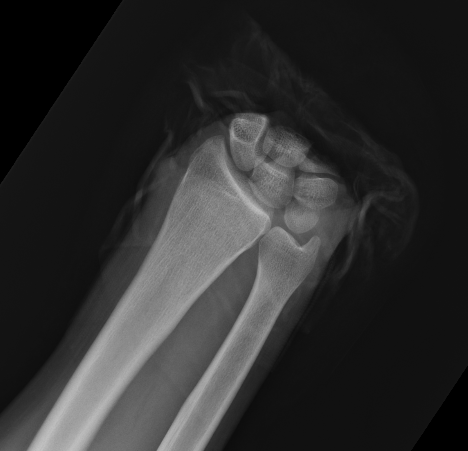

Midcarpal Replantation

Major Limb Replantation

Definition

Proximal forearm / elbow joint / arm

Issues

1. Usually avulsion or crush injuries types with extensive muscle injury

2. Amputations proximal to metacarpal level have significant muscle bulk

- high risk of myonecrosis and subsequent infection

- immediate arterial inflow is necessary

- need patient hydration and osmotic diuresis to protect kidneys

3. Functional outcome related to level of amputation

Technique

Rapid skeletal stabilisation

- at least one artery must be revascularised

- then follow sequence for digit

- extensive fasciotomies always indicated

- any exposed vessels must be covered by rotation flap etc